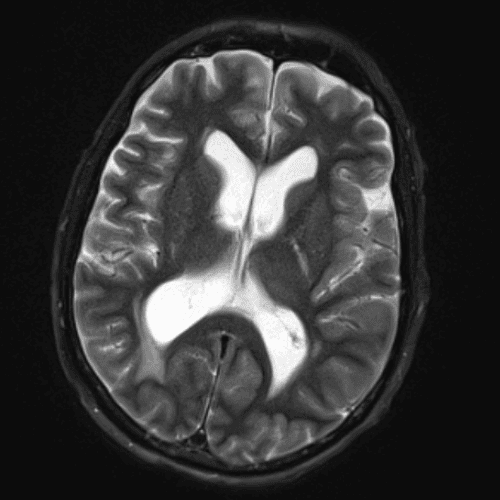

๋ฏธ๋ฌ˜ํ•˜๊ฑฐ๋‚˜ ์–ด๋ ค์šด ์‚ฌ๋ก€์™€ ์ผ๋ถ€ ์ •์ƒ ์‚ฌ๋ก€๋ฅผ ํฌํ•จํ•˜์—ฌ ๋‹น์ง์„ ์‹œ๋ฎฌ๋ ˆ์ด์…˜ํ•ฉ๋‹ˆ๋‹ค.

50 ์‚ฌ๋ก€